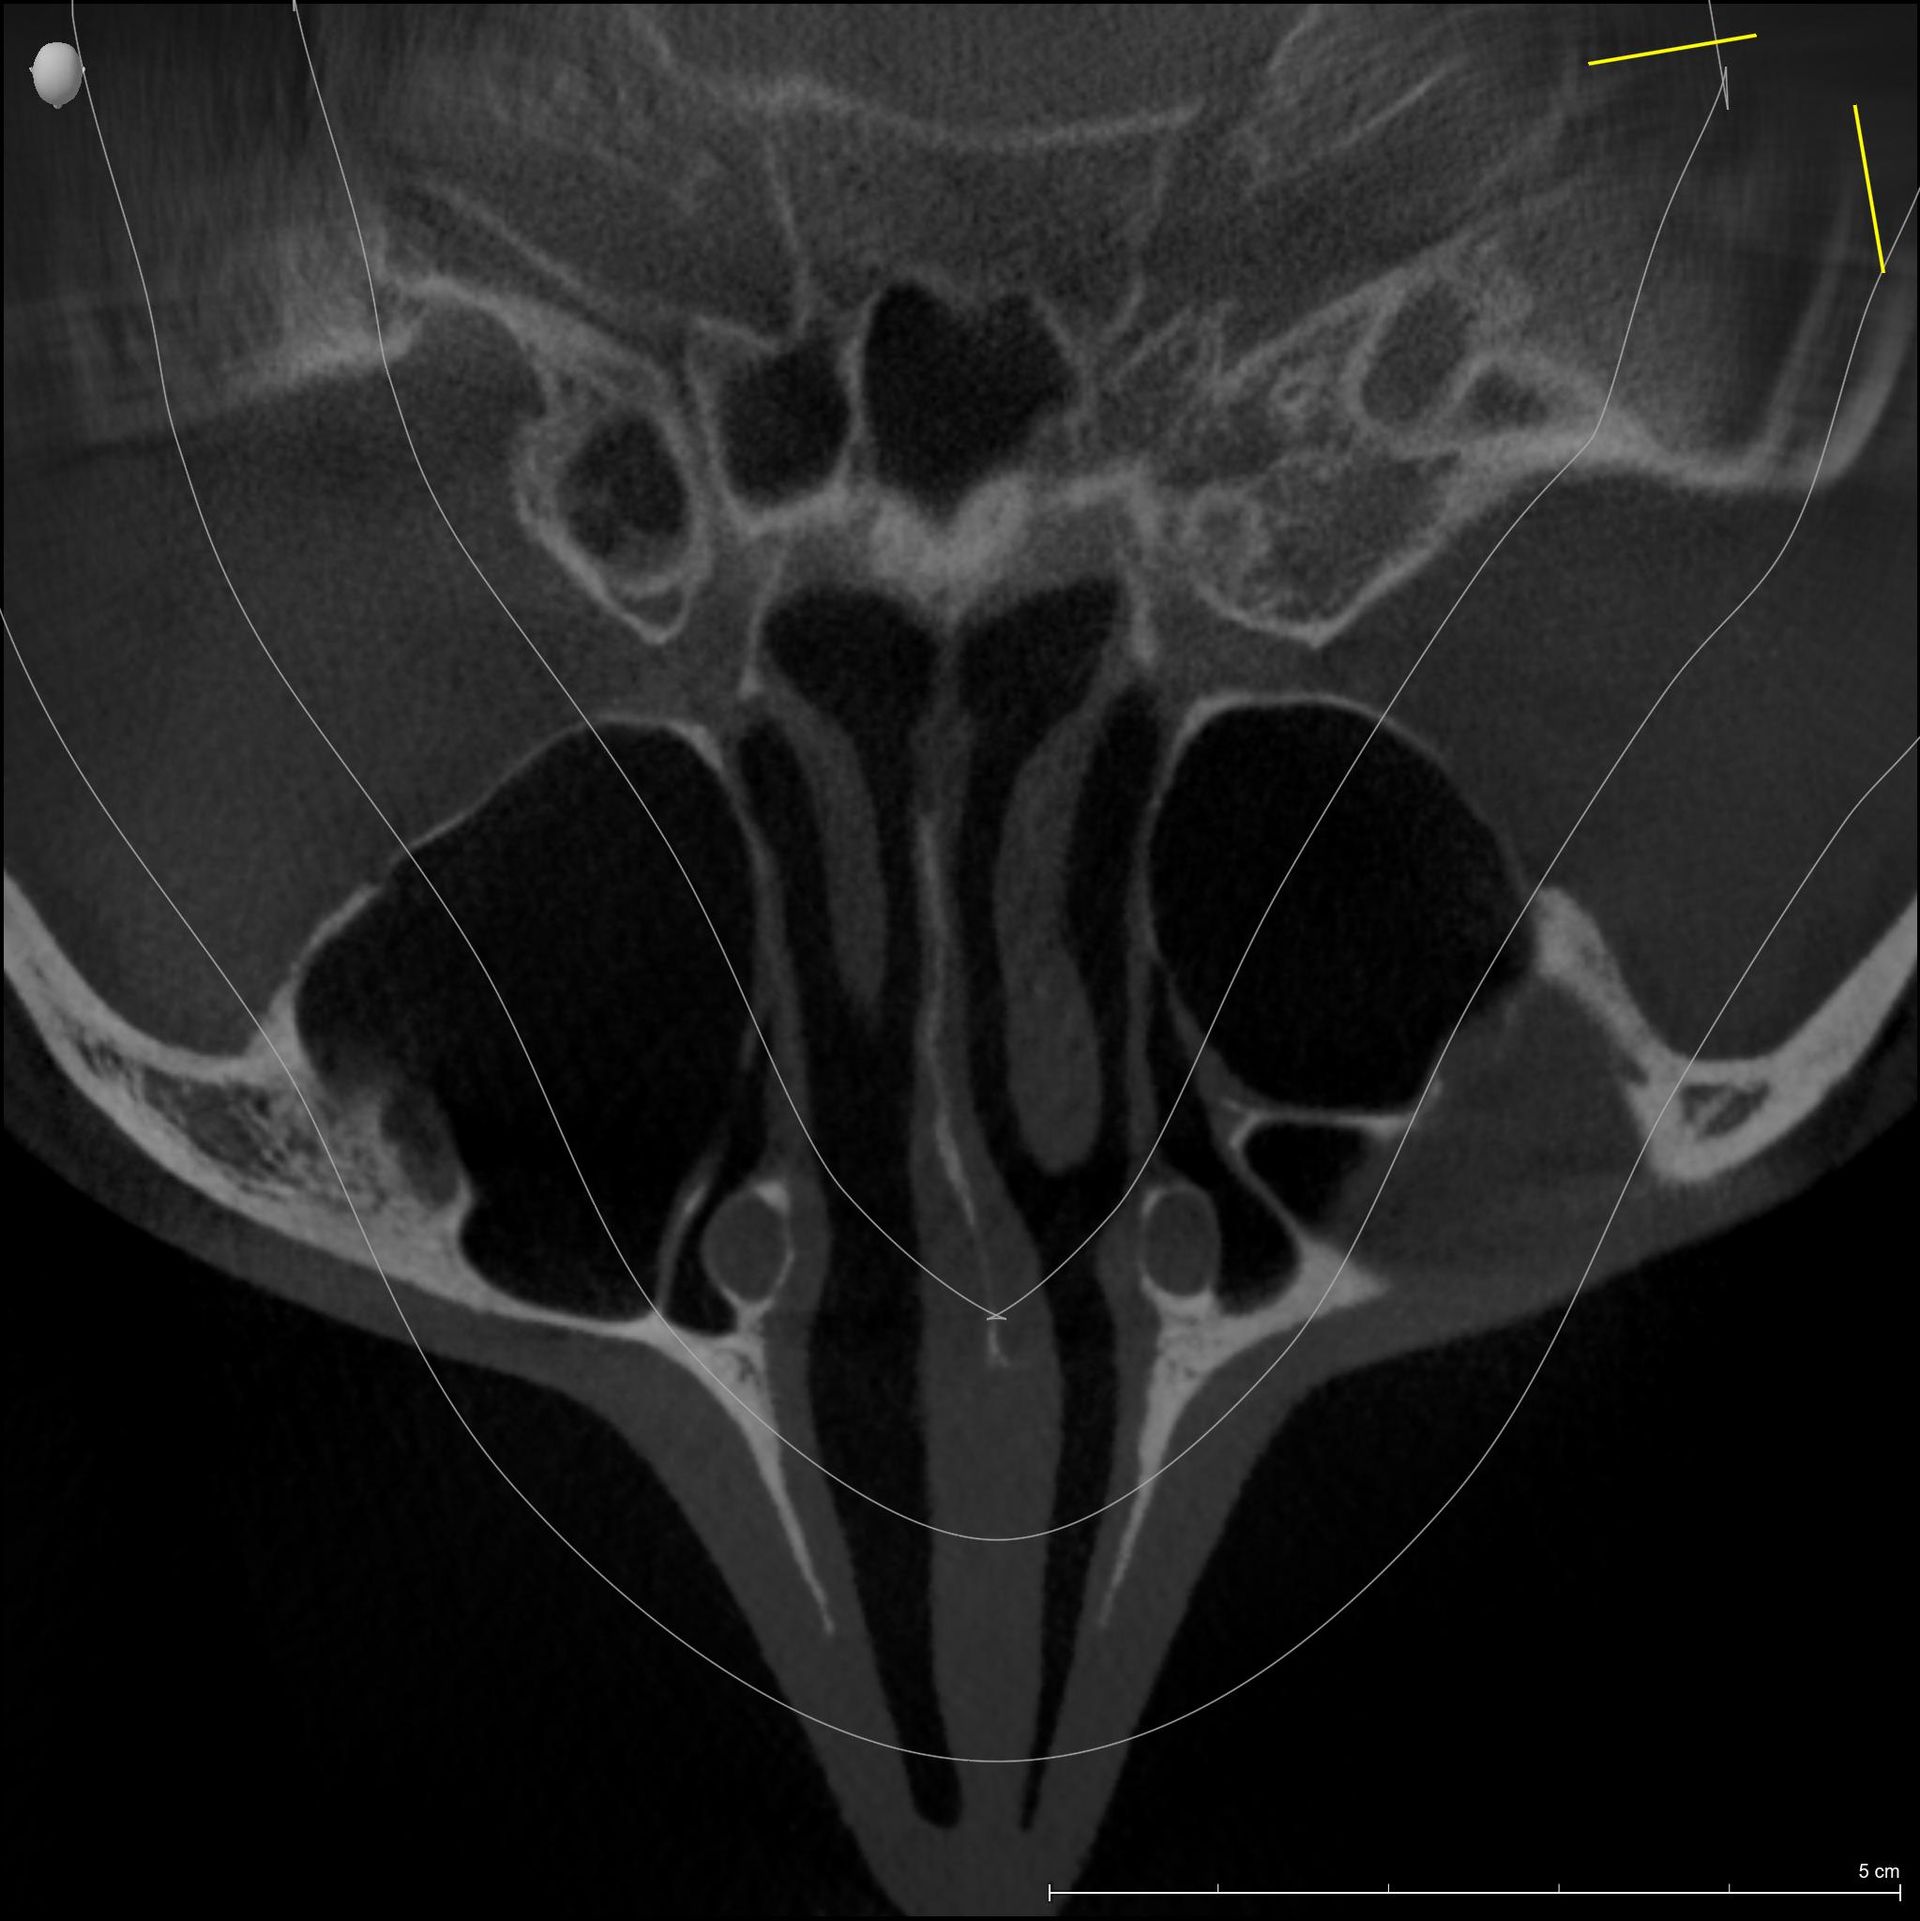

Dentalscan 3D-TC Cone Beam

Esame diagnostico che permette di valutare, con precisione, la densità ossea mascellare e mandibolare, richiesto dai dentisti, in quanto indispensabile prima di un intervento di implantologia.

Trova indicazione anche in ortodonzia per lo studio dei denti inclusi, soprannumerari ed ectopici e in endodonzia.

La nostra struttura utilizza un’apparecchiatura radiologica di ultima generazione (Sirona Orthophos SL 3 D), che permette, in un’unica soluzione, di effettuare esami di arcate dentarie, cefalometrici e volumetrici 3 D).

Il nuovo sensore, a conversione diretta, garantisce precisione, con immagini più nitide, dettagliate e a bassissima emissione di raggi X (da 5 a 20 volte inferiore rispetto alla TC tradizionale); con bassissima dose per il paziente; quindi molto adatta ai pazienti più piccoli.

La funzione 3D, permette la visualizzazione completa delle strutture dentarie, ossee, in tre dimensioni, con ottima risoluzione di contrasto per lo studio dei tessuti molli.